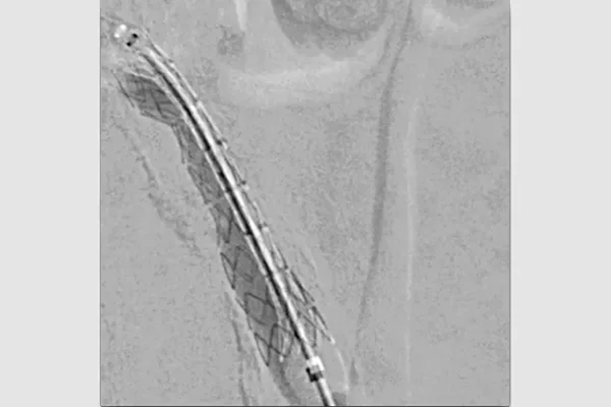

钙化髂动脉的支架输送

Viabahn VBX导管介绍